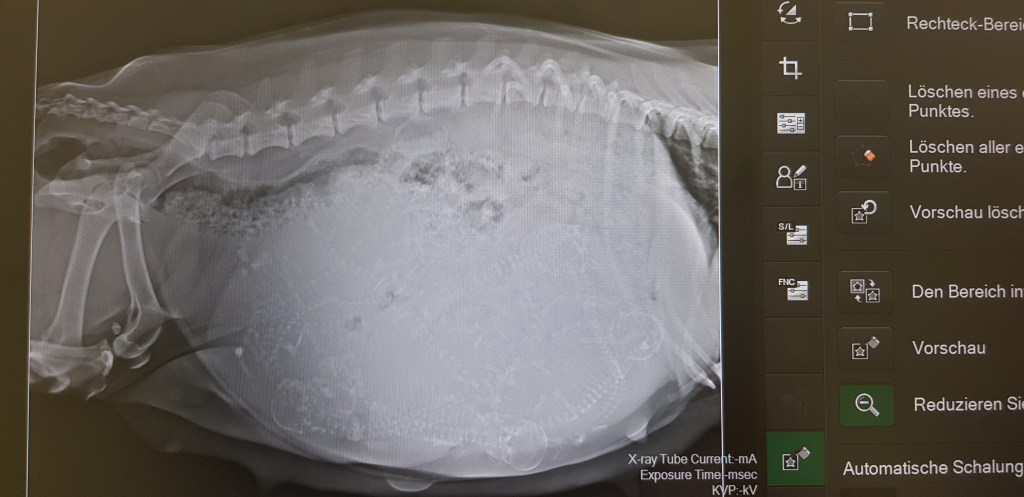

Für uns war klar … entweder sind es wenige fette Brummer oder eben viele Welpen. Zur Abklärung haben wir uns auf den weg zum Röntgen gemacht.

Es ist heiß und Aminata leidet unter der Riesen Wampe, wir sind der Meinung es geht bald los!